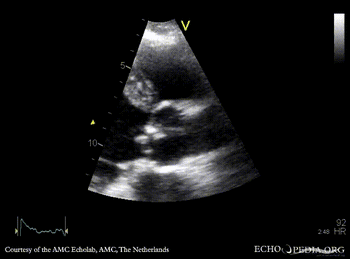

A4CH: dilated left ventricle A5CH: vegetations on aortic valve, dilated left ventricle